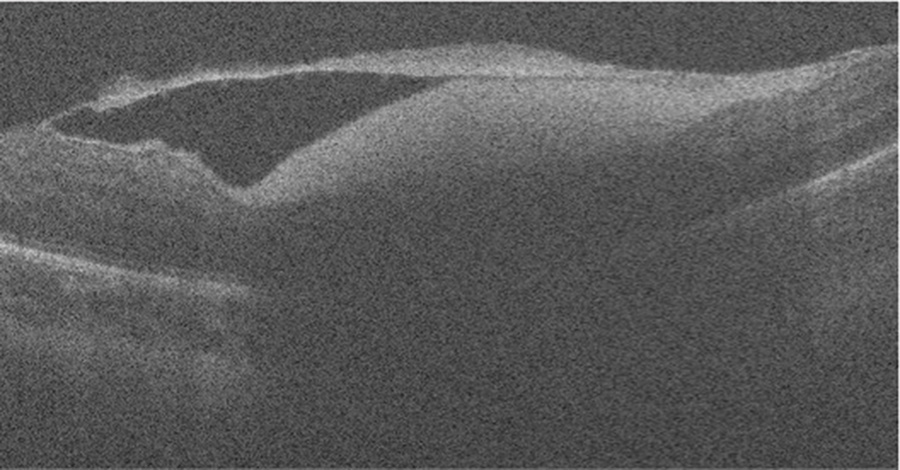

De senaste åren har anpassade ögonbottenkameror för fotografering av spädbarn och småbarn blivit tillgängliga och möjliggör fotodokumentation av ögonbottenfynd, vilket underlättar samråd mellan ögonläkare [50]. Högupplösande bildteknologi (optisk koherenstomografi, OCT), har också blivit tillgänglig för undersökning av barn. Med OCT-kamera kan man få två- och tredimensionell avbildning av näthinnans olika cellager samt övergången mellan åderhinnan, näthinnan och glaskroppen, vilket inneburit en ökad förståelse av både normal och patologisk utveckling [51]. Bildfynden stödjer hypotesen att upprepade kraftiga dragningar från glaskroppen förorsakar näthinneblödningar och uppsplittring av näthinnelagren som ses vid AHT [22-24]. Figur 1-5 visar ögonbottenfotografier samt OCT-bild från barn som utsatts för AHT.

Figur 5. Horisontell skanning av centrala delen av makula med handhållen OCT-kamera. Bilden visar en relativt normal näthinna nasalt, en preretinal blödning temporalt och en förtjockad, delvis avlossad glaskroppsyta (hyaloid hinna) posteriort. Med tillstånd från professor Cynthia Ann Toth, MD, PhD, Duke Eye Center, Durham (tidigare publicerad i: Seider MI, Tran-Viet D, Toth CA. Retin Cases Brief Rep. 2016;10(3):283-5).